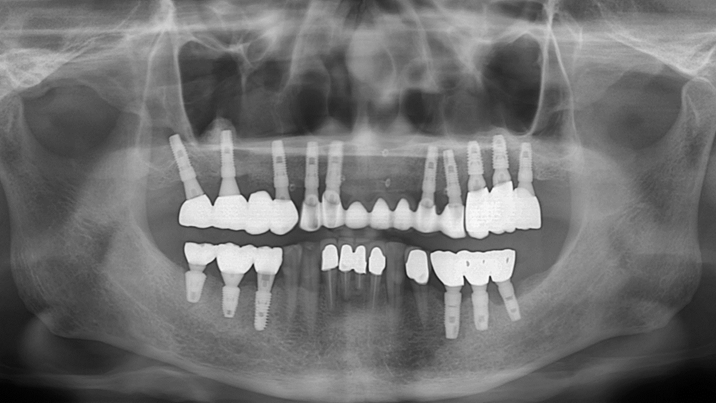

Clinical case: Peri-implantitis treatment case using titanium or NiTi brush

- Courtesy of Dr. Dae-Hee Lee, South Korea -

Dr. Dae-Hee Lee,Maxillary Anterior,Peri-implantitis,Bone regeneration,Aesthetic zone,#21,#22,GBR,Titanium Brush Set